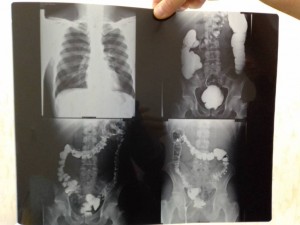

Срочно нужна помощь на приобретения лекарства 2000 тр , денег нет ,недавно лежал в хирургии 1 гороцкой больнице прогноз не утишительный , выписался до нового года а проблема осталось поставили диагноз : воспаления кишечьника, спайки, и язвы желудка если кто не равнодушен помогите , Киви кошелек +79012830491 за ранее спасибо просто боли не выносимо

Деньги на лекарства - IMG_20191209_163357.jpg

Деньги на лекарства - IMG_20191209_163328.jpg